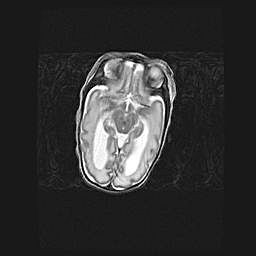

Лейкомаляция с кистозно-глиозной дегенерацией головного мозга.

Возраст: 2 месяца 25 дней

Вес: 6400 г

Окружность головы: 40 см

Срок гестации: 41 неделя

Лейкомаляцию относят к ишемически-гипоксическим повреждениям головного мозга, диагностируемым у новорожденных. При лейкомаляции в головном мозге обнаруживают очаги некроза, возникшие после тяжелой гипоксии и нарушения кровотока. В процессе морфогенеза очаги проходят три стадии: 1) развития некроза, 2) резорбции и 3) формирования глиозного рубца или кисты. Перивентрикулярная лейкомаляция (ПЛ) встречается примерно в 12% случаев среди новорожденных, обычно – у недоношенных детей, причем, частота ее зависит от массы, с которой младенец появился на свет. Наибольшее число малышей страдает лейкомаляцией, если масса при рождении 1500-2500 г.